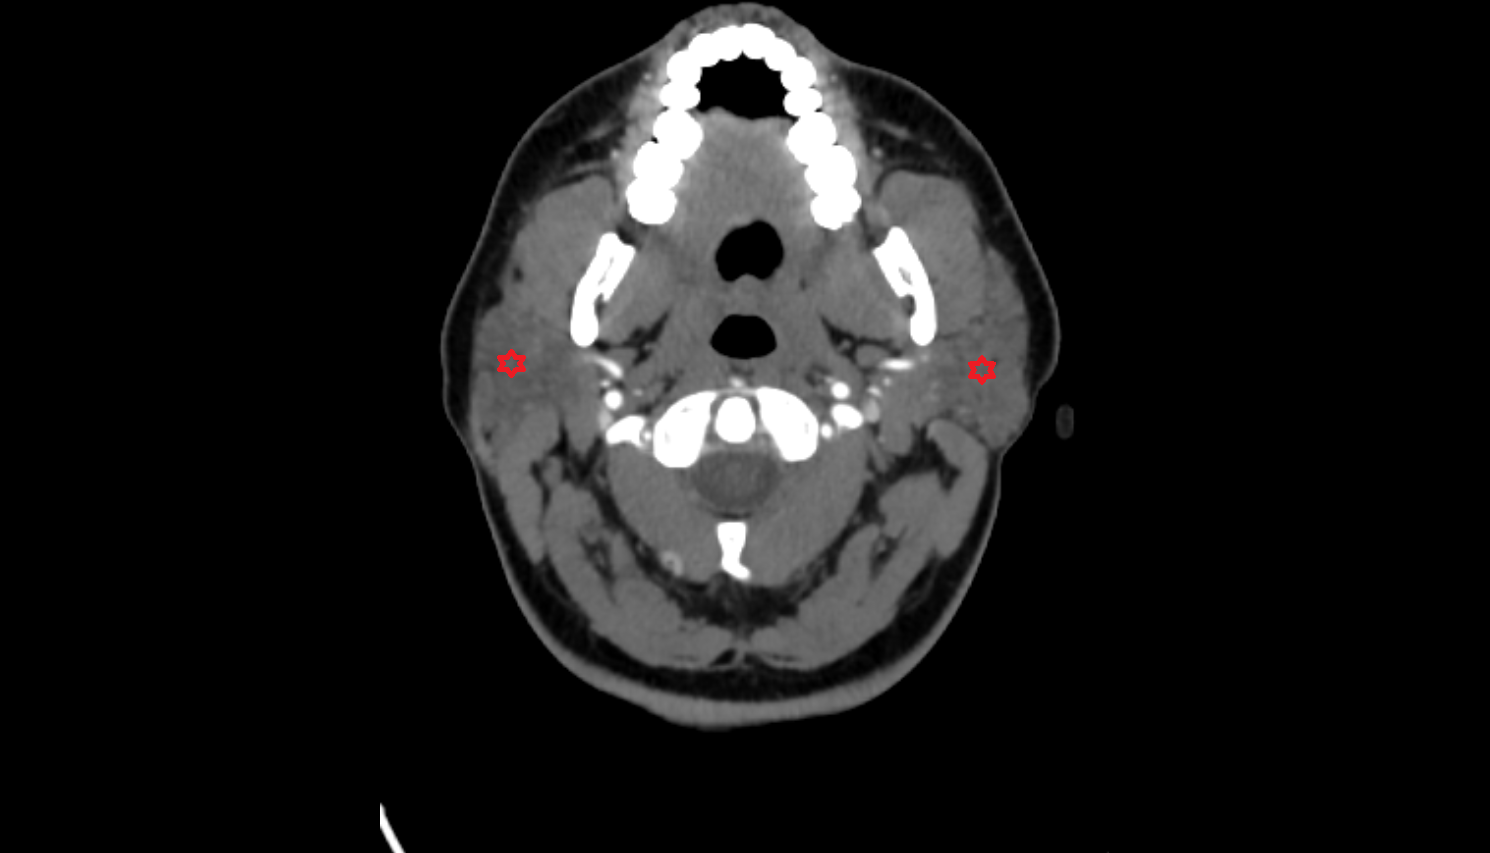

- Parotid gland

- Masseter muscle

- Lateral pterygoid muscle

- Submandibular lymph nodes

- Superficial parotid lymph nodes

- Deep parotid lymph nodes